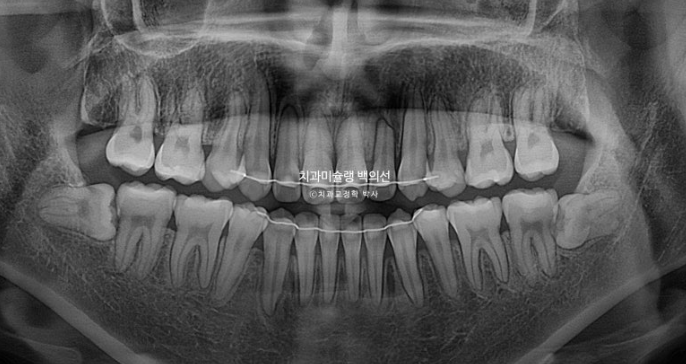

25.10

2년 가까운 기간동안 위 앞니 두 개 정도에 치근흡수가 보입니다.

치근평행도는 좋습니다.